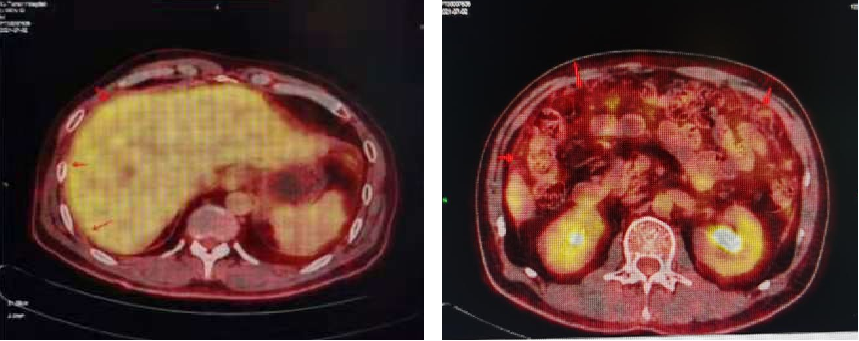

肝周少量积液,肝缘腹膜增厚,大网膜絮状增厚,轻度FDG代谢,考虑腹膜转移。

2021-06至今 TAS-102+贝伐珠单抗。

复查CT:腹膜增厚,提示腹膜转移,较前变化不大。